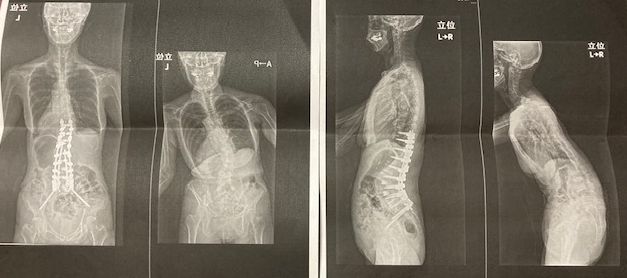

従来少し前傾と左傾をしていた脊椎が、私が後期高齢者入りした今年3月に、前屈と左へ傾斜が急に悪化。

痛みも強くなり、歩行困難と日常生活への大きな支障をきたすようになりました。

「変性後側弯症」改善のための「脊椎後方矯正固定術」

結局、脊椎の変性後側弯症ということで、手術するしかないことに。

それに、もうかなり長く付き合っている「脊柱管狭窄症」があり、その解消のための手術も同時に行われることに。

手術名は、「脊椎後方矯正固定術」及びそれに付随する「骨移植術」というもの。

脊椎の後ろ側を削り、金属の棒を背骨代わりに複数用いて、脊椎間を人工骨と削除粉砕した骨で埋め繋いでいくものです。

この手術で、同時に脊柱管狭窄症は排除されることになります。